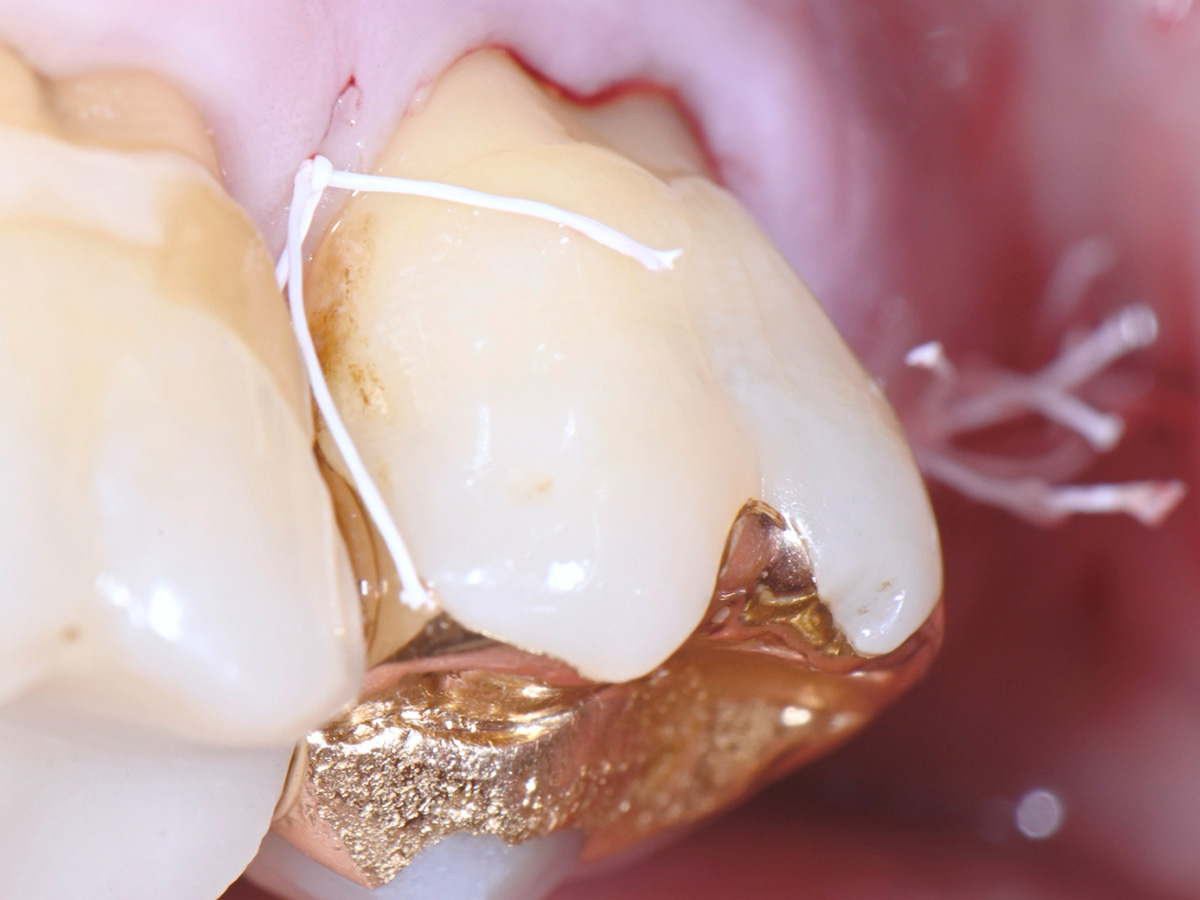

Abbildung 2

Klinische Ausgangssituation